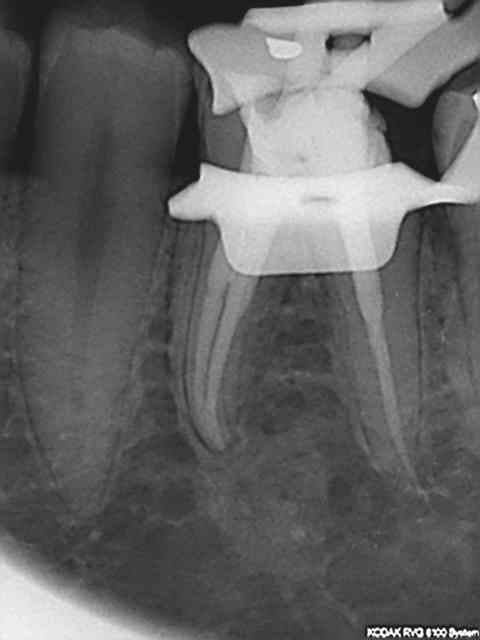

plus d'une heure pour essayer de sauver ces 37 et 38...

mais etait ce vraiment suffisant? cicatrisation possible?

60 mn environ pour ces 2 là, le canal mv2 augmente le temps d'exéctution de 15 à 30 mn surtout si l'entrée est proche du mv1. Il n'y a pas photo entre la préparation canalaire du r25 VS f2 protaper.